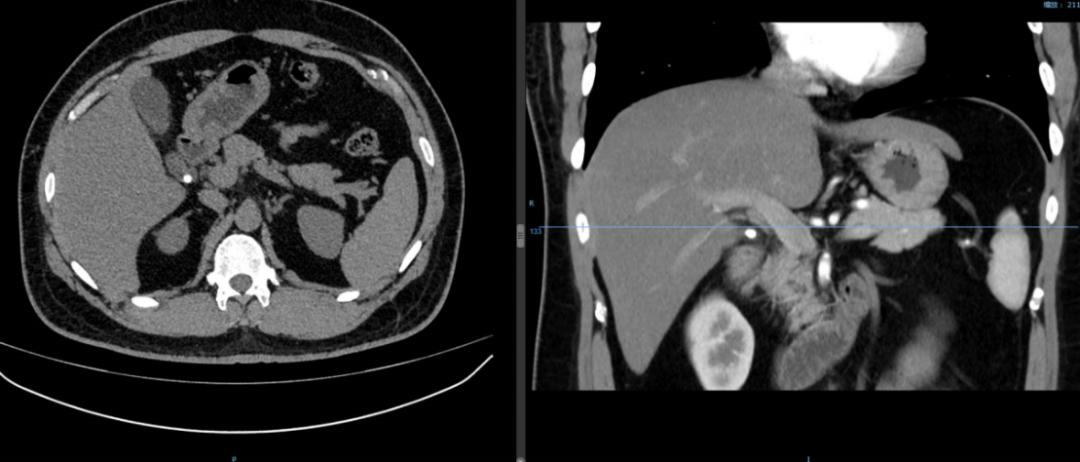

47岁男性,胆囊结石多年,未予重视。与朋友聚餐后突发腹痛并身目黄染急诊入院,检查提示胆囊最大结石直径超过4cm,胆总管下端小结石堵塞致肝内外胆管扩张,总胆红素超过300μmol/L(正常值为小于21μmol/L),行“腹腔镜胆囊切除+胆总管切开探查取石+T管引流”,术后症状缓解,黄疸逐步消退。

60岁女性,胆囊结石多年,一直未予重视,亦无规律随访复查。因偶然体检发现胆囊结石、胆囊占位就诊,完善检查后不排除胆囊癌,遂入院行“胆囊癌根治术(胆囊切除+肝部分切除+肝外胆管切除+区域淋巴结清扫+胆管-空肠吻合术)”,术后病例提示低分化胆囊腺癌,目前密切随访治疗中。